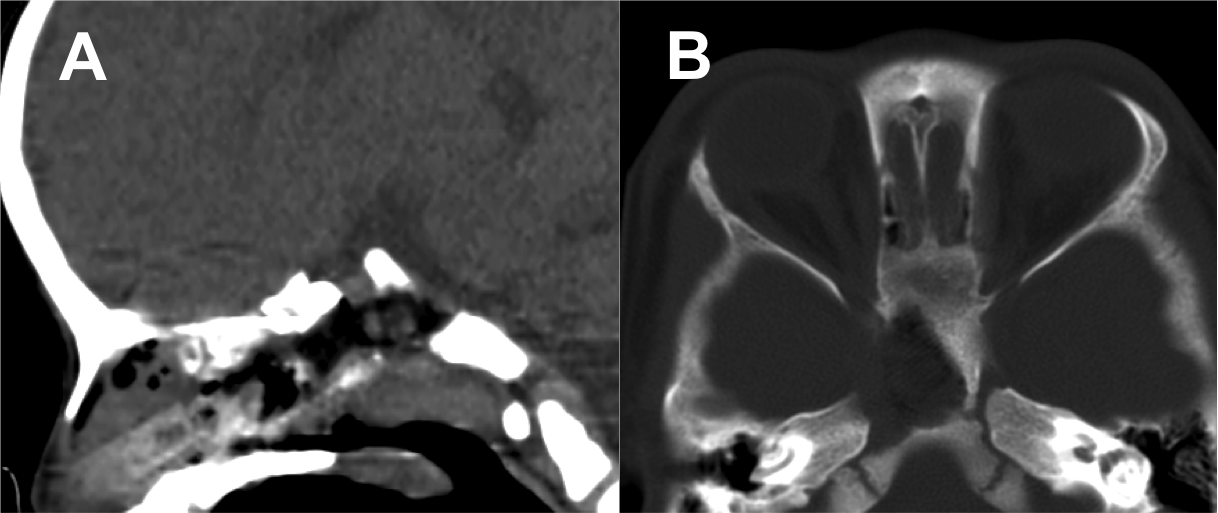

Introducción: La cirugía endoscópica endonasal se ha convertido en una herramienta fundamental para el manejo de patologías que comprometen la base de cráneo. En casos bien seleccionados, estas técnicas permiten resecciones quirúrgicas con una menor morbilidad sin comprometer los principios oncológicos de resección. Con el desarrollo de instrumental especializado, nuevas tecnologías y la experiencia de los cirujanos, la cirugía endoscópica endonasal se usa cada vez más en cirugía de base de cráneo en niños.

Objetivo: presentar una serie de casos de pacientes pediátricos con tumores de base de cráneo manejados con cirugía endoscópica endonasal.

Diseño: Estudio observacional descriptivo de tipo serie de casos. Metodología: se describe la experiencia con pacientes pediátricos llevados a cirugía endoscópica endonasal para manejo de tumores de base de cráneo en el Instituto Nacional de Cancerología entre julio de 2014 y diciembre de 2016.

Resultados: Fueron intervenidos 8 pacientes entre los 2 y 14 años, con una edad promedio de nueve años y un seguimiento promedio de 16 meses. En el 75% se hizo una resección total del tumor. Un paciente requirió una reintervención y un paciente fue sometido a radiocirugía post-operatoria. 1 paciente falleció a pesar de múltiples intervenciones, quimioterapia y radioterapia.

Conclusión: La cirugía endoscópica endonasal para tumores de base de cráneo puede ser utilizada de forma segura en los pacientes pediátricos, es una técnica que en casos bien seleccionados pueden ofrecer excelentes resultados disminuyendo la morbilidad y complicaciones de las técnicas abiertas.